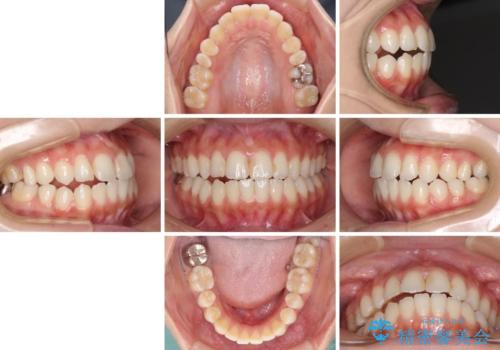

- オープンバイトのため、話しているときの見た目が気になるとのことで来院された患者様です。

下顎骨は左側にシフトしており、咬み合ったときには奥歯と前歯の一部しか接触していない状態でした。

骨格的な左右差は歯列矯正は改善できないため、上下歯列が全体的に接触することをゴールとしてインビザラインにて矯正治療を行うこととしました。

前歯のデコボコの解消と並行して上下の奥歯を圧下させるようにすることで、前歯を接触させるように計画しました。

上下の隙間に舌が入り込むことがオープンバイトの原因であったため、舌の筋肉のトレーニングも並行して行い、後戻りの抑制を図りました。